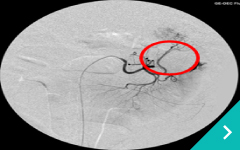

IVRとは、レントゲン透視(X線)や超音波などの画像を使いながら、カテーテルという細い管を体内に通して、病気のある部位を治療する方法です。開胸や開腹をせずに治療できることから、体への負担が少なく、多くのわんちゃん・ねこちゃんにとって優しい選択肢となります。

門脈体循環シャント:異常な血管にコイルやプラグを入れて、血流を正常化します。

肝臓腫瘤に対する

肝動脈塞栓術